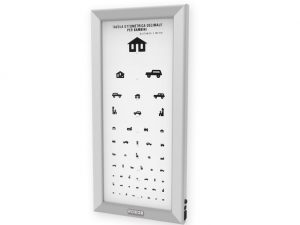

Tavole optometriche, Tavole optometriche a LED ultrapiatte

OTTOTIPO ULTRAPIATTO A LED – Pediatrico

455,00 € (555,10 € IVA incl.) -